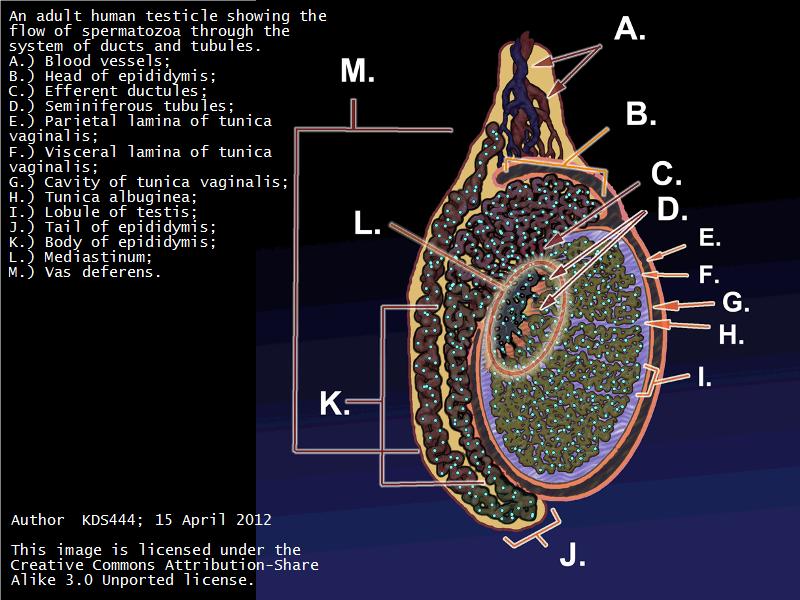

Testis

Slide 84

Testis

- Tunica albuginea

- Lobuli

- Seminiferous tubuli

- Epididymus

- Ductus deferens

Tunica albuginea

- Thick fibrous CT capsule

- Forms septae

- Divide testis into lobuli

Lobuli

- Pyramidal shaped compartments

- Contain 1 - 4 seminiferous tubules each within

Epididymus

- Long convoluted duct

- With fibrous covering

- Inside visceral layer of tunica vaginalis testis

Ductus deferens

Also vas deferens

Ductus deferens

- Muscular duct with small lumen